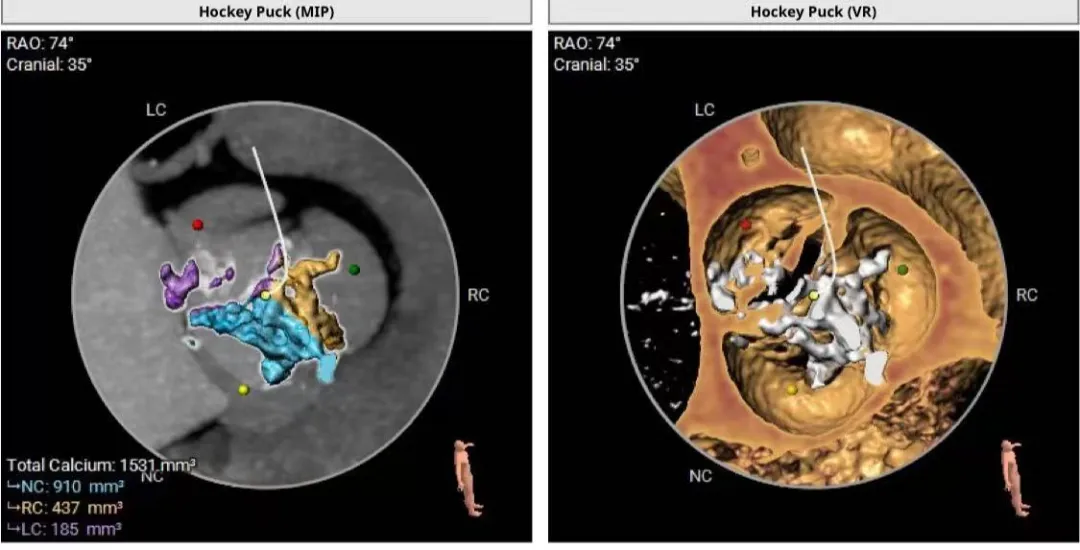

第一位患者为一名76岁老人,患有严重的主动脉瓣狭窄合并广泛钙化。其瓣膜组织已严重硬化,不仅极大增加了导管通过和瓣膜释放的难度,更存在钙化碎片脱落导致脑卒中的高风险。此外,严重钙化还可能影响人工瓣膜的稳定锚定,极易引发瓣周漏、传导阻滞等严重并发症。在传统手术中,此类患者因心功能差、合并症多,术后死亡率极高,被视为手术“禁区”。

术前评估“侦察兵”:医学影像学科团队对两位患者的主动脉根部进行了细致入微的参数测量,包括瓣环直径、冠脉开口高度及钙化分布情况等。通过3D重建技术,为手术团队提供了详尽的解剖结构图。

在重度主动脉瓣反流合并四叶瓣畸形患者手术中,团队依托术前CT三维重建提供的精准数据,精心选择带有外裙边设计的TaurusOne瓣膜,以尽可能减少术后可能出现的瓣周漏。在释放过程中,术者凭借毫米级的精细操控和多年临床经验,将人工瓣膜精准锚定于“黄金区域”。术后即刻经食道超声确认:人工瓣膜位置完美,反流完全消失,且未对心脏传导系统造成影响。